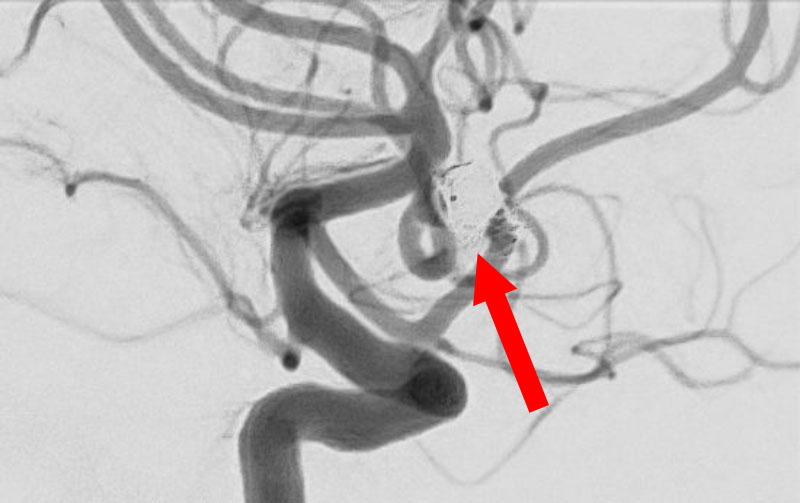

No.1630 手術前

No.1630 手術中

No.1630 手術後